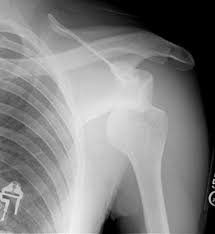

Botbreuk (fractuur)

In het schoudergewricht zitten verschillende botstukken: de kop van de bovenarm, de kom van het gewricht, het sleutelbeen en het schouderblad. Komt er te veel kracht op een bot, dan kan het breken. Een breuk kan ook ontstaan door langdurig herhaalde bewegingen of door een ziekte in het bot. Een gebroken schouder is pijnlijk en gaat vaak gepaard met een zwelling en/of bloeduitstorting. Soms is er te zien dat een van de botten in een vreemde stand staat. Het is niet mogelijk om een gebroken bot te belasten.